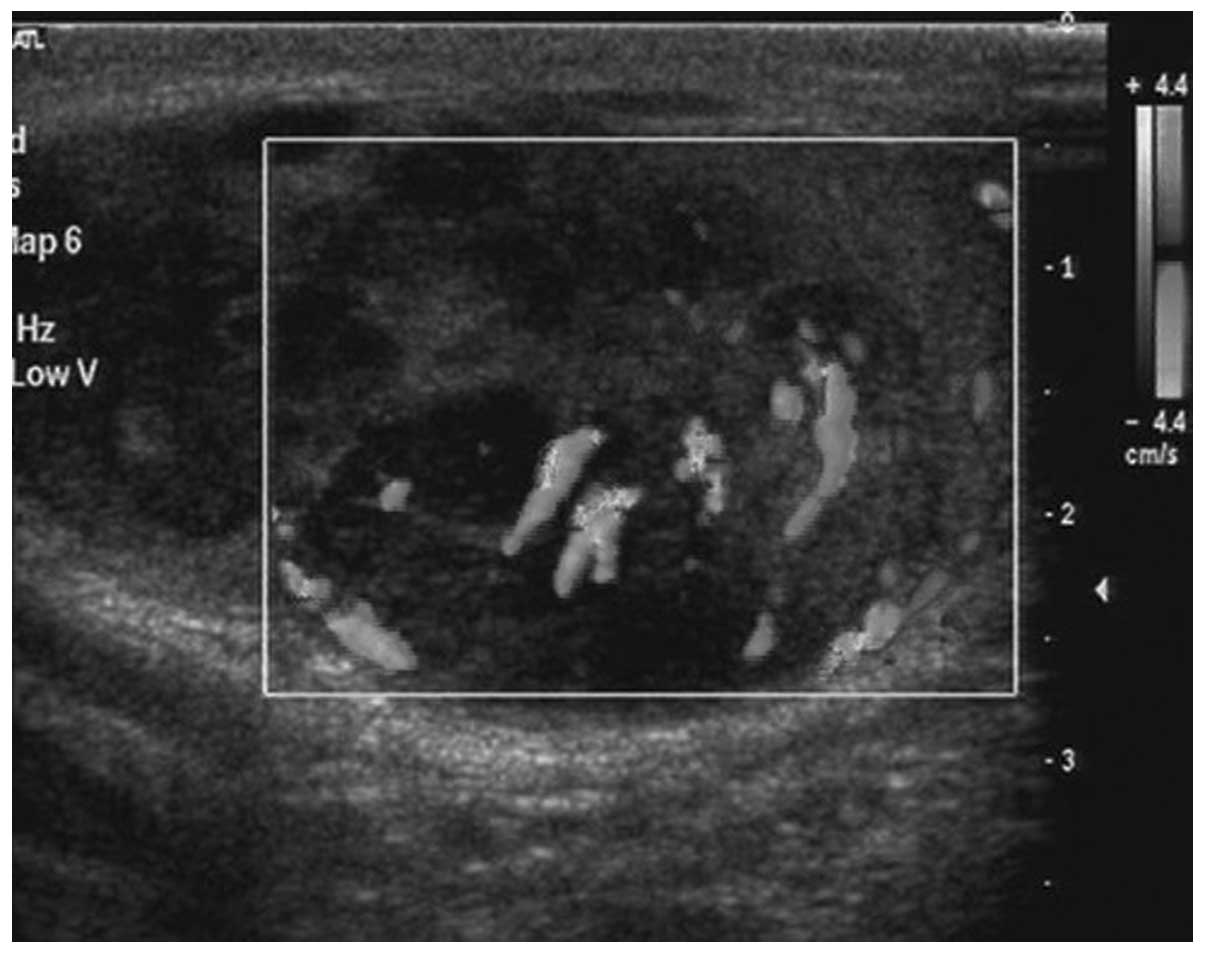

Primary desmoplastic small round cell tumor of the testis: A case report and review of the literature

Desmoplastic small round cell tumors (DSRCTs) are extremely rare and mainly affect adolescents and young adults. The tumors are usually involved with the abdominal area and/or the pelvic peritoneum. Only a small number of cases have been reported concerning DSRCTs of the testicular region. The present study reports a case of DSRCT of the testis with radical orchectomy and systemic chemotherapy, leaving the patient disease-free for 14 months. However, the patient died of multiple metastasis 12 months later. Furthermore there is a review of the English literature to analyze the incidence, site of origin, imaging and pathological characteristics of DSRCT.

Figure 3